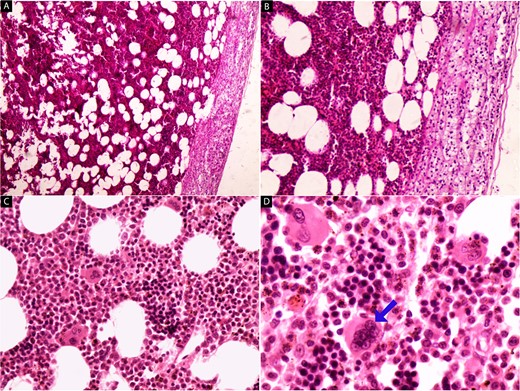

We report the case of a 45-year-old female, who presented to our hospital because of a mass on the right adrenal gland that was discovered incidentally during a periodic echocardiogram without any symptoms on the patient. The patient declared a history of excisional biopsy for a benign breast mass, a medical history of medication-controlled hypertension for 5 years, and Type 2 diabetes for 10 years but the family history was unremarkable. Laboratory investigations, including complete blood count and biochemical markers, were within normal limits. Imaging studies were performed, including contrast-enhanced computed tomography (CT) of the abdomen. The CT scan revealed a large, well-defined, heterogeneous mass measuring 13 × 12 × 9.5 cm, located in the right adrenal gland. The mass contained areas of high attenuation, suggesting recent hemorrhage, along with fat-density areas consistent with adipose tissue (Fig. 1). There were no signs of invasion into adjacent structures or lymphadenopathy. Based on the clinical presentation and radiological findings, the provisional diagnosis was a hemorrhagic giant adrenal myelolipoma. The patient underwent a right open adrenalectomy to address a large mass and minimize potential complications such as hemorrhage. Intraoperatively, a large, encapsulated mass was found in the right adrenal gland. The mass was carefully dissected from surrounding tissues, and the adrenal gland was removed and sent to the pathology department. There were no intraoperative complications. Upon gross examination, a mass with a total weight of 44.5 g was observed, measuring 15 × 10.5 × 5 cm. The mass displayed encapsulation and exhibited a rubbery to cystic consistency, with areas of hemorrhage evident. The cut surface revealed a heterogeneous composition, ranging in color from yellow to black and presenting a gelatinous texture. Multiple sections of the specimen were subsequently submitted for further analysis (Fig. 2). Microscopic examination revealed a mixture of mature adipose tissue and hematopoietic elements, including myeloid and erythroid cells. Focal areas of hemorrhage and hemosiderin deposits were observed within the tumor (Fig. 3), consistent with the radiological findings. Histopathological examination confirmed the diagnosis of a hemorrhagic adrenal myelolipoma. There was no evidence of malignancy. The patient had an uneventful postoperative recovery and was discharged on the 5th day after surgery. Follow-up at 6 months showed no complications, and imaging studies demonstrated no evidence of tumor recurrence. The patient continues to be asymptomatic and is under regular surveillance.

Gross examination of the right adrenal mass (44.5 g, 15 × 10.5 × 5 cm). Encapsulated, rubbery to cystic consistency with hemorrhage foci. Heterogeneous, yellow to black, gelatinous cut surface.